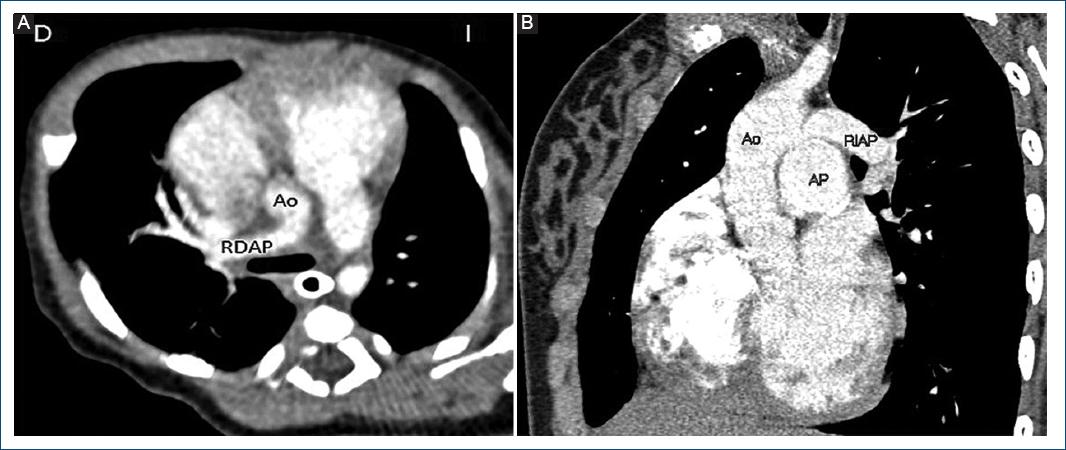

Figura 1 A: OARDAP. B: OARIAP. OARDAP: origen anómalo de la rama derecha de la arteria pulmonar; RDAP: rama derecha de la arteria pulmonar; RIAP: rama izquierda de la arteria pulmonar; AP: arteria pulmonar; AAo: arteria aorta; OARIAP: origen anómalo de la rama izquierda de la arteria pulmonar.

Figura 2 A: TC vista axial de nuestro primer caso con OARDAP. B: TC vista anterior de nuestro cuarto paciente con OARIAP. TC: tomografía computarizada; AO: aorta; RDAP: rama derecha de la arteria pulmonar; AP: arteria pulmonar; RIAP: rama izquierda de la arteria pulmonar.

Se encontró soplo sistólico III/VI paraesternal izquierdo alto. Se realizó ecocardiograma y tomografía axial computarizada (TAC), las cuales informaron hipertensión arterial pulmonar (HAP) suprasistémica, persistencia del conducto arterioso (PCA) y origen anómalo de la rama derecha de la arteria pulmonar (OARDAP) (Fig. 2A).

Presentó taquicardia y dificultad respiratoria. Por ecocardiograma se diagnosticó PCA y OARIAP, confirmándose por angio-TAC, en donde se apreció también estenosis de la rama izquierda y compresión del bronquio principal izquierdo que condicionó atelectasia (Fig. 2B).